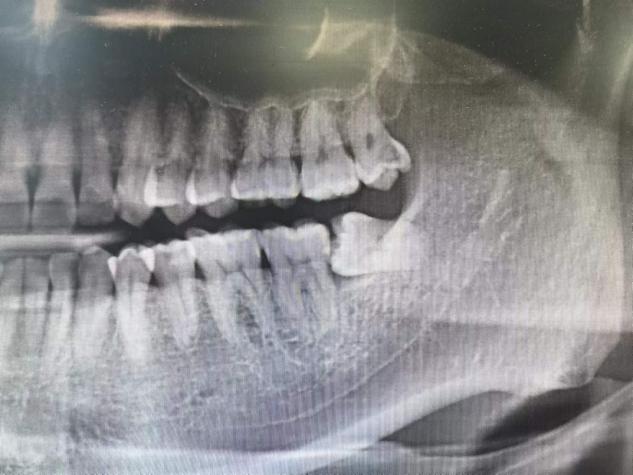

智齿,是我们口腔中的第三磨牙,从正中线开始数的第八颗牙齿,一般在18岁左右萌出,是我们口腔中的最后一颗,所以大家称它为智齿。由于现代人们饮食越来越精细,咀嚼锻炼不充分,导致颌骨逐渐退化变小,骨量不足,所以它常常没有正常的位置,以阻生的形式存在。

1.智齿阻生

位置方向异常,导致智齿不能萌出。

4.邻牙吸收

智齿由于生长空间不足,可能导致邻牙压迫性吸收,最终可能两颗牙都要拔除。